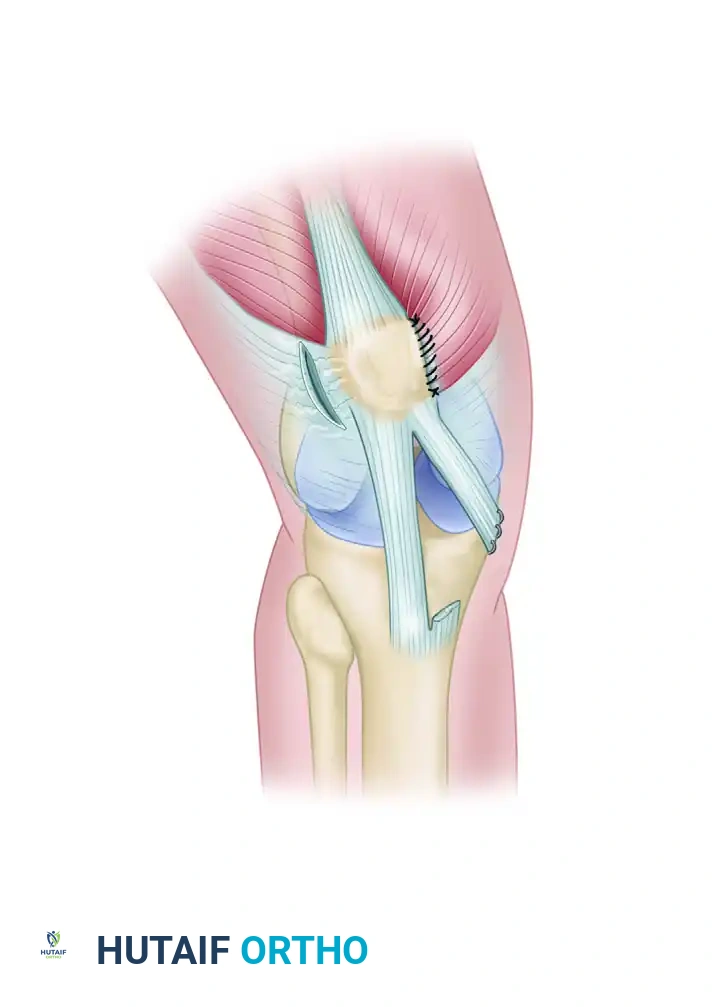

6. Suturing the MPFL

"Let's secure this ligament back where it belongs."

- Suture Placement: Pass No. 2 or stronger nonabsorbable sutures through the patella tunnels (or suture anchor eyelets). Then, meticulously weave these sutures through the advanced MPFL tissue.

* Attachment Point: Critically, the MPFL should be sutured to the anteromedial surface of the patella, not the posteromedial surface. This ensures the correct vector of pull and avoids medial patellar tilt.

7. Tensioning the Repair

"This is arguably the most critical step for functional outcomes."

- Knee Flexion: Position the knee at 45 to 60 degrees of flexion. This is the sweet spot for tensioning.

- Tensioning: With the knee in this position, carefully tie down the sutures, applying appropriate tension.

> Surgical Warning: Over-tensioning can lead to medial patellar pain, chondral overload, and restricted flexion. Under-tensioning will result in persistent instability. The goal is to allow for smooth patellar tracking without excessive lateral excursion, but also without undue medial restriction.

8. Assessing the Repair and Closure

"Let's test our work."

- Range of Motion: Put the knee through a full range of motion, from full extension to deep flexion. Observe the patellar tracking. The patella should track smoothly in the trochlea without subluxation or excessive lateral pull, and without undue resistance to flexion. Perform a patellar apprehension test again.

- Final Soft Tissue Closure: The remaining free lateral edge of the MPFL tissue (retinaculum) is sewn down to the patellar soft tissue with a running 2-0 absorbable suture. This reinforces the repair and closes the soft tissue layers.